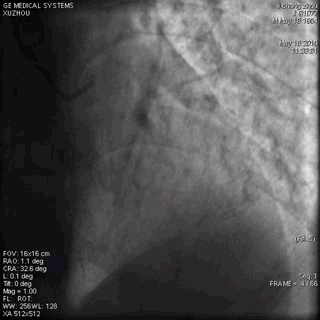

正常,冠脉造影正常。

(左冠脉造影1)